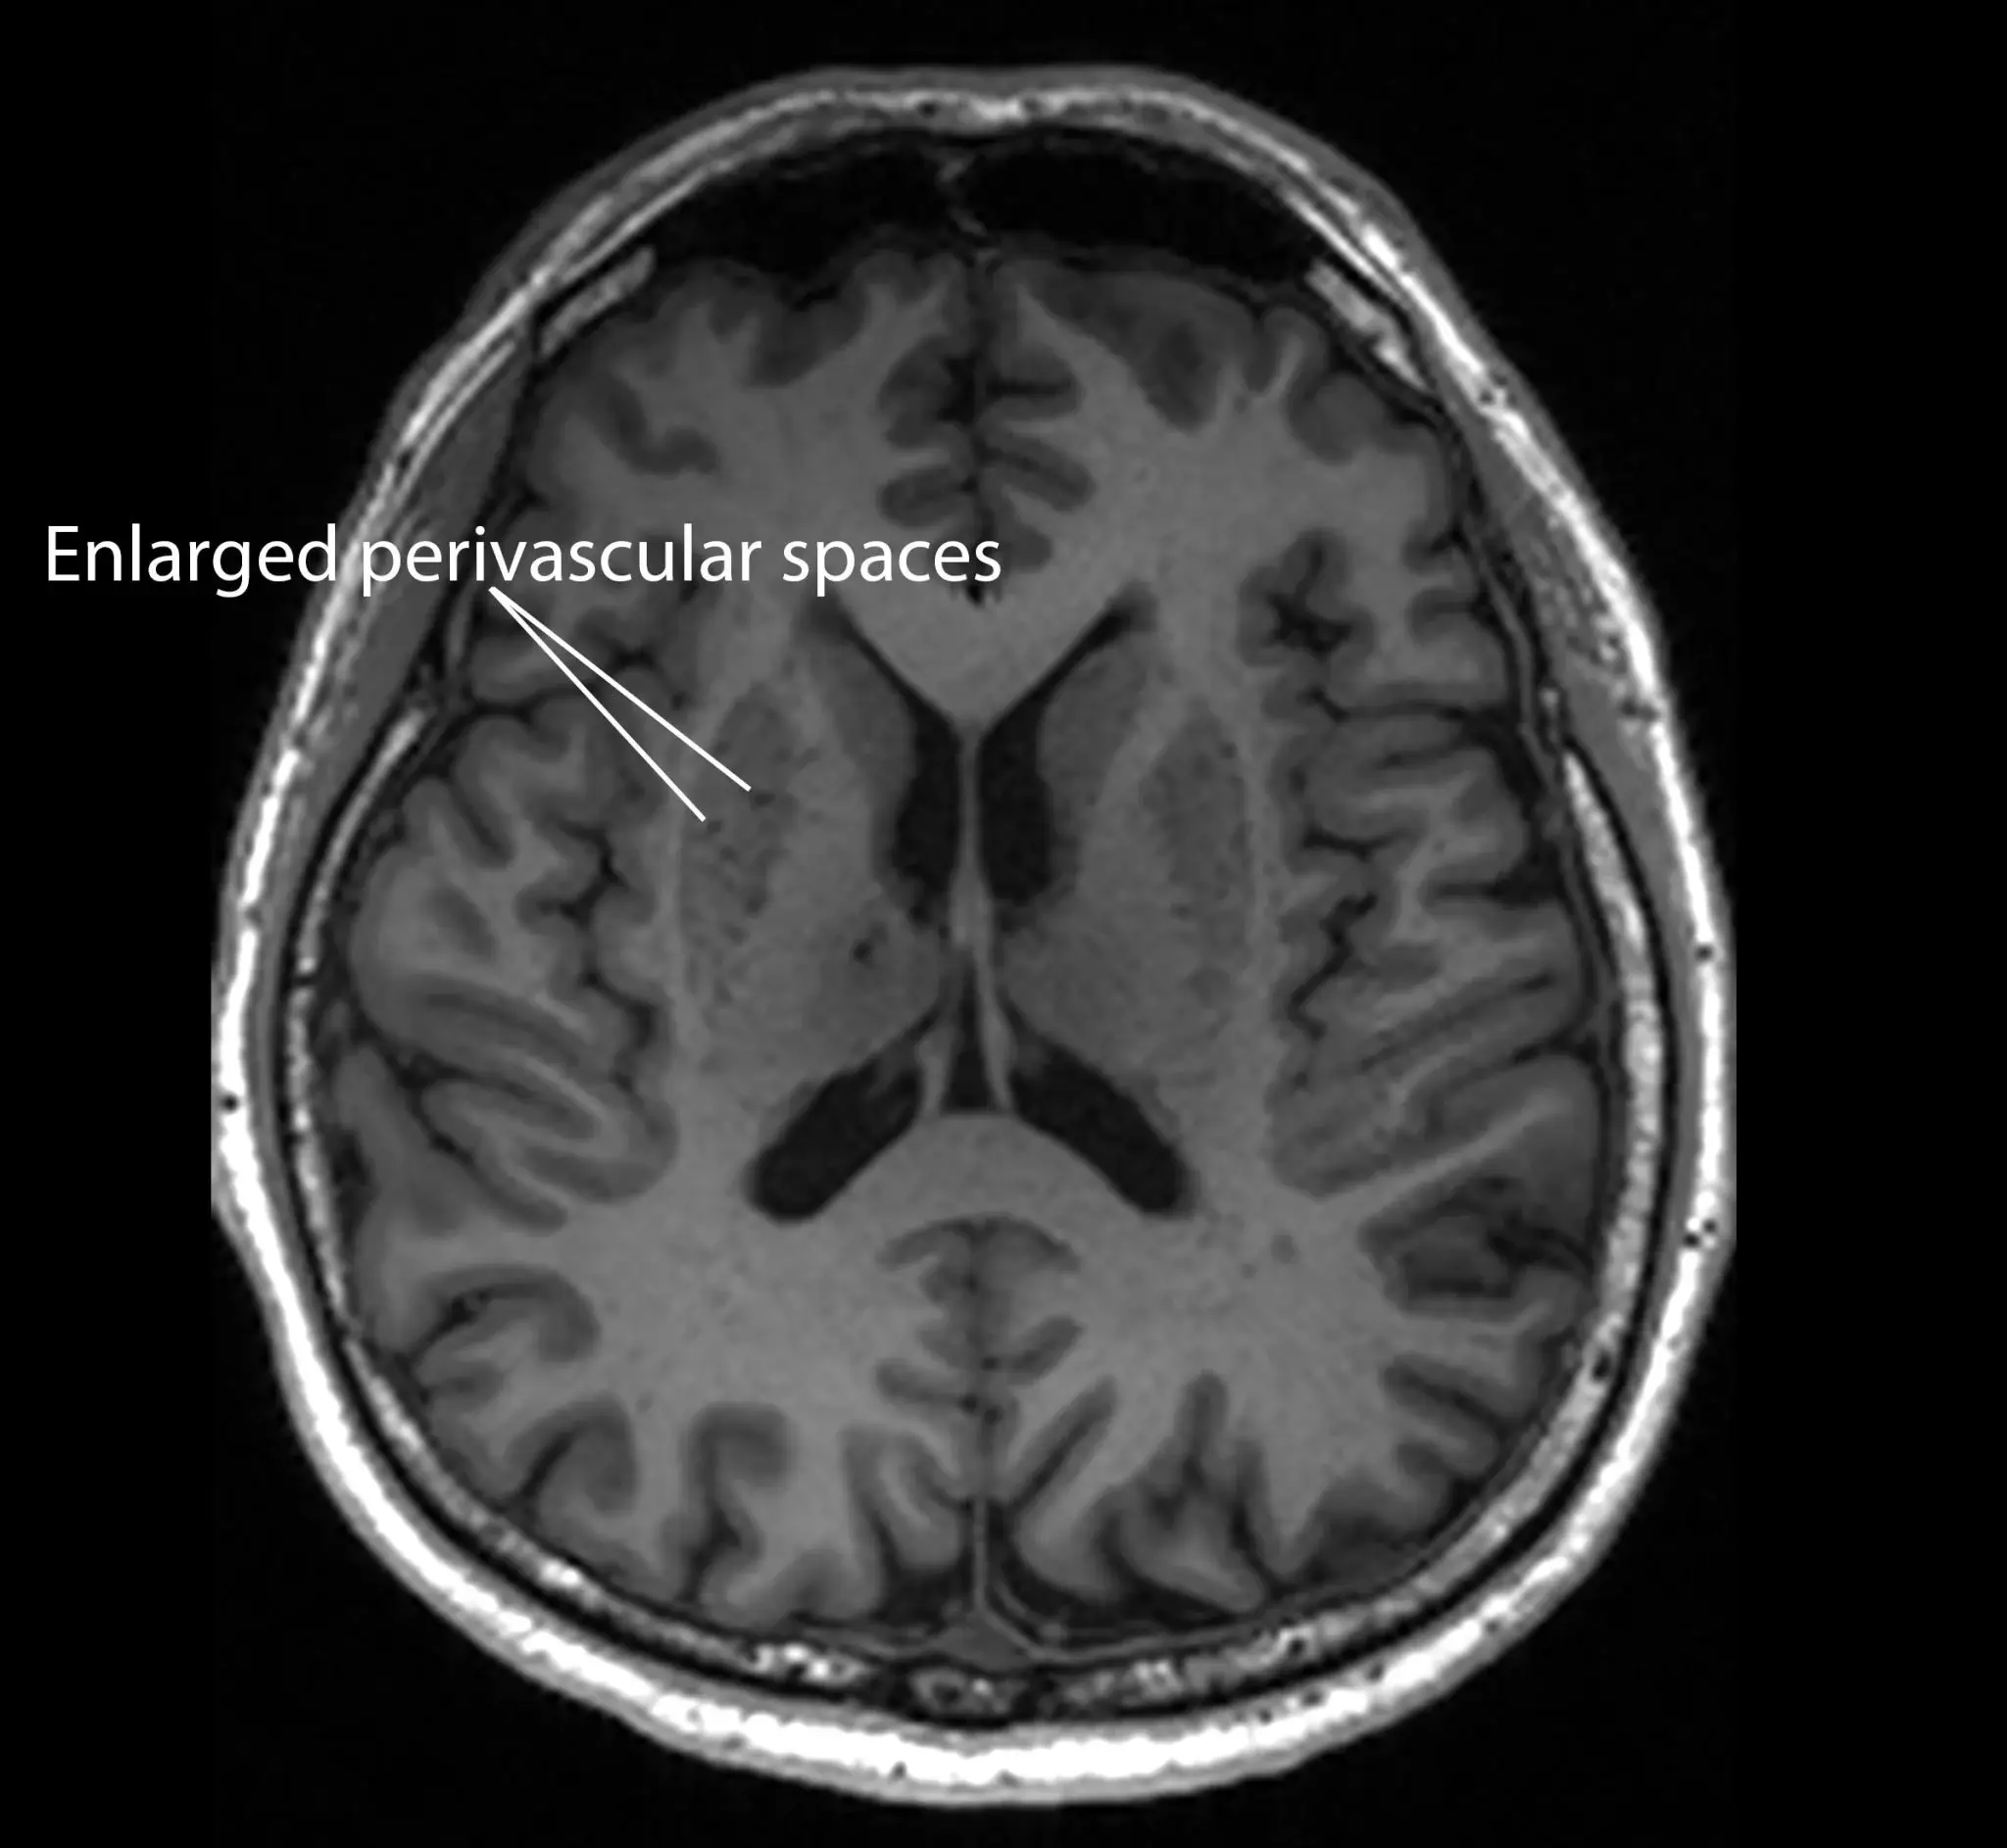

Known as enlarged perivascular spaces, they are visible on routine Magnetic Resonance Imaging (MRI) scans.

These enlarged spaces can be linked to other signs of Alzheimer’s, including higher amyloid plaques, more tau tangles and signs of brain cell damage.

This suggests the clogging happens before major brain damage, making it a promising early detection marker.